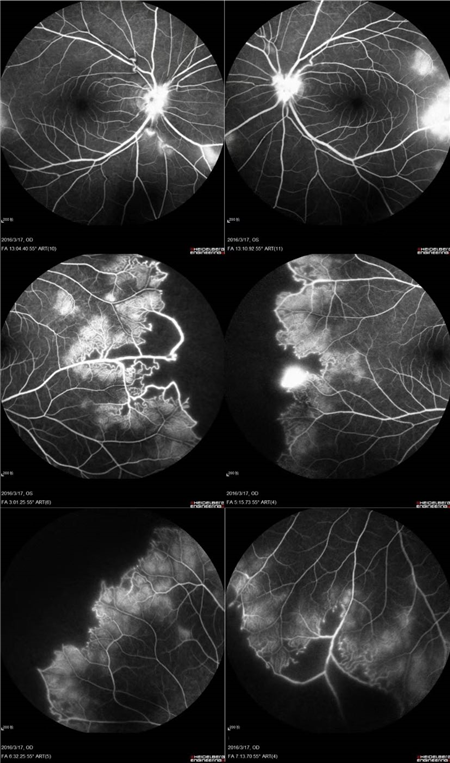

北京希玛眼科医院:IRVAN综合征引起的黄斑裂孔(案例分享)

特发性视网膜血管炎、动脉瘤和视神经视网膜炎综合征(Idiopathic Retinal Vasculitis, Aneurysm, and Neuroretinitis syndrome,简称IRVAN综合征)是一种病因不明的较为少见的视网膜血管炎性疾病,此病症常在30-40岁发病且多为女性发病。在发病的前期,如果进行及时有效的治疗干预,预后效果多数较好。但一拖再拖,错过最好的治疗时间,可引起严重的并发症。在这里提醒大家,一定要密切关注自己眼部突发情况的出现,警惕眼前突然发生黑影飘动,视力下降的情况,尽早就医。

经过详细的眼底检查后,患者被诊断为IRVAN综合征引起的右眼黄斑裂孔,张风院长带领医生团队为患者施局右眼玻璃体切除+剥膜+眼内光凝+气液交换手术,经过半个月的恢复,患者右眼术后视力由术前0.3-达到0.6-的状态,且裂孔呈逐渐闭合状态。